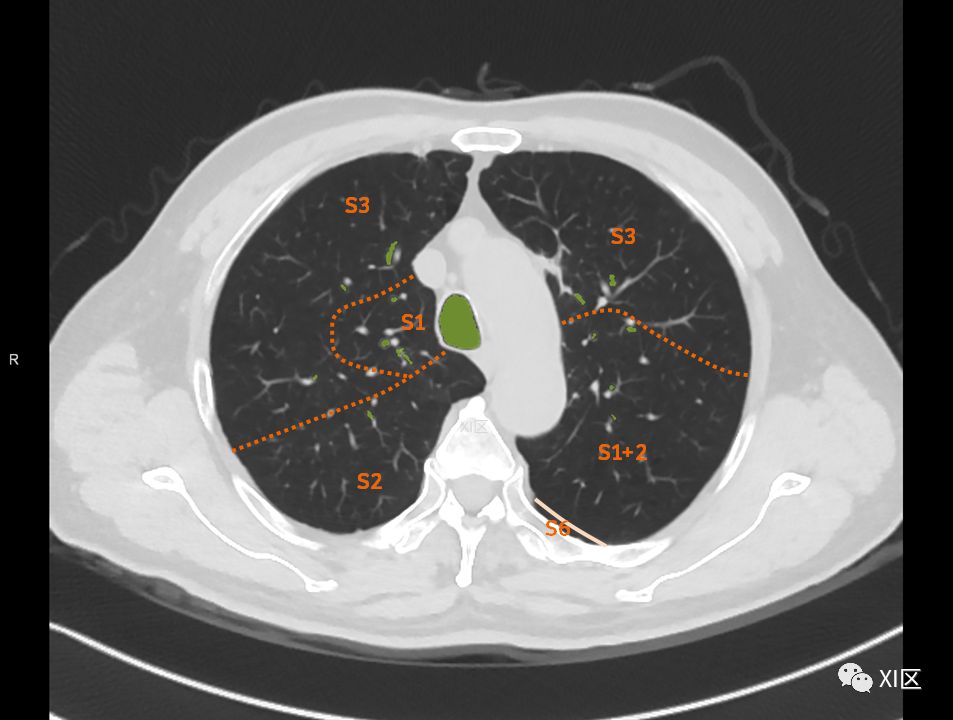

肺的分段

肺的断层分段示意图

在进行肺的分段时,可以上下视察浏览,沿着相应气管的走形可以更容易准确地进行分段。